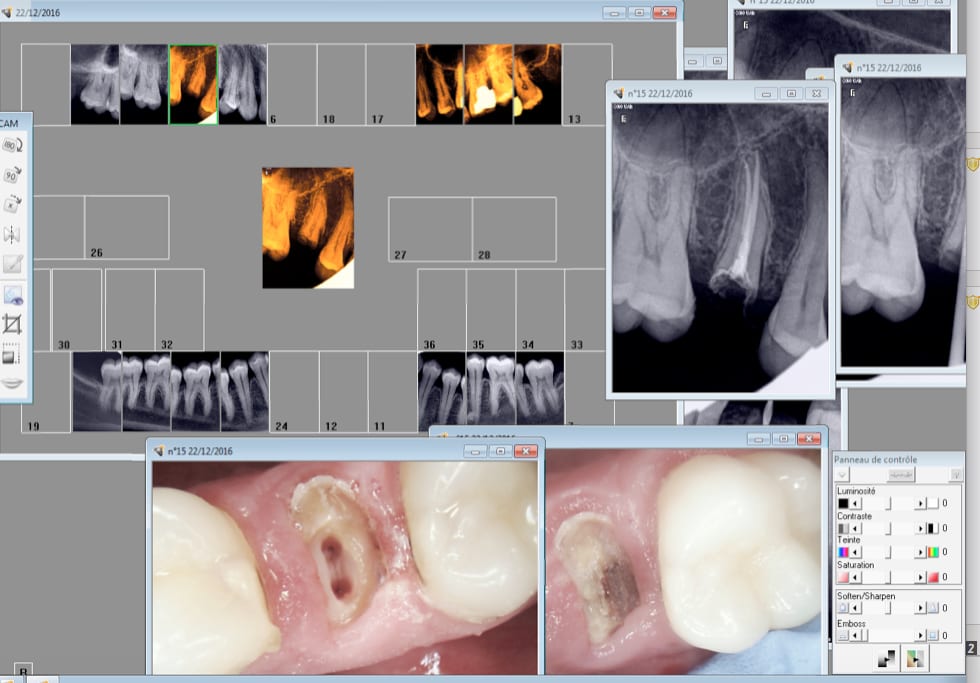

Nouveau patient, douleurs diffuses status radio endo 25, 30 mn

Magnifique endo à reprendre sur 47. Donc 2 couronnes à suivre. -)

Tiens pareil nouvelle patiente. Bis répétita. -)

Et une autre toujours nouveau patient premier RDV 30 mn.